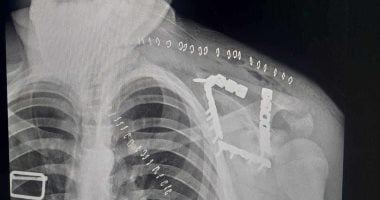

جح فريق طبي بمستشفى التأمين الصحي بالفيوم في التعامل مع واحدة من الحالات النادرة والمعقدة في جراحات العظام، وتمكنوا من إنقاذ شاب في عملية جراحية استمرت لساعات، داخل المستشفي بعد إصابته بكسر مفتاح بلوج الكتف يتطلب جراحة دقيقة. كان استقبل مستشفى التأمين الصحي بالفيوم شابًا يبلغ من العمر 17 عامًا، يعا...